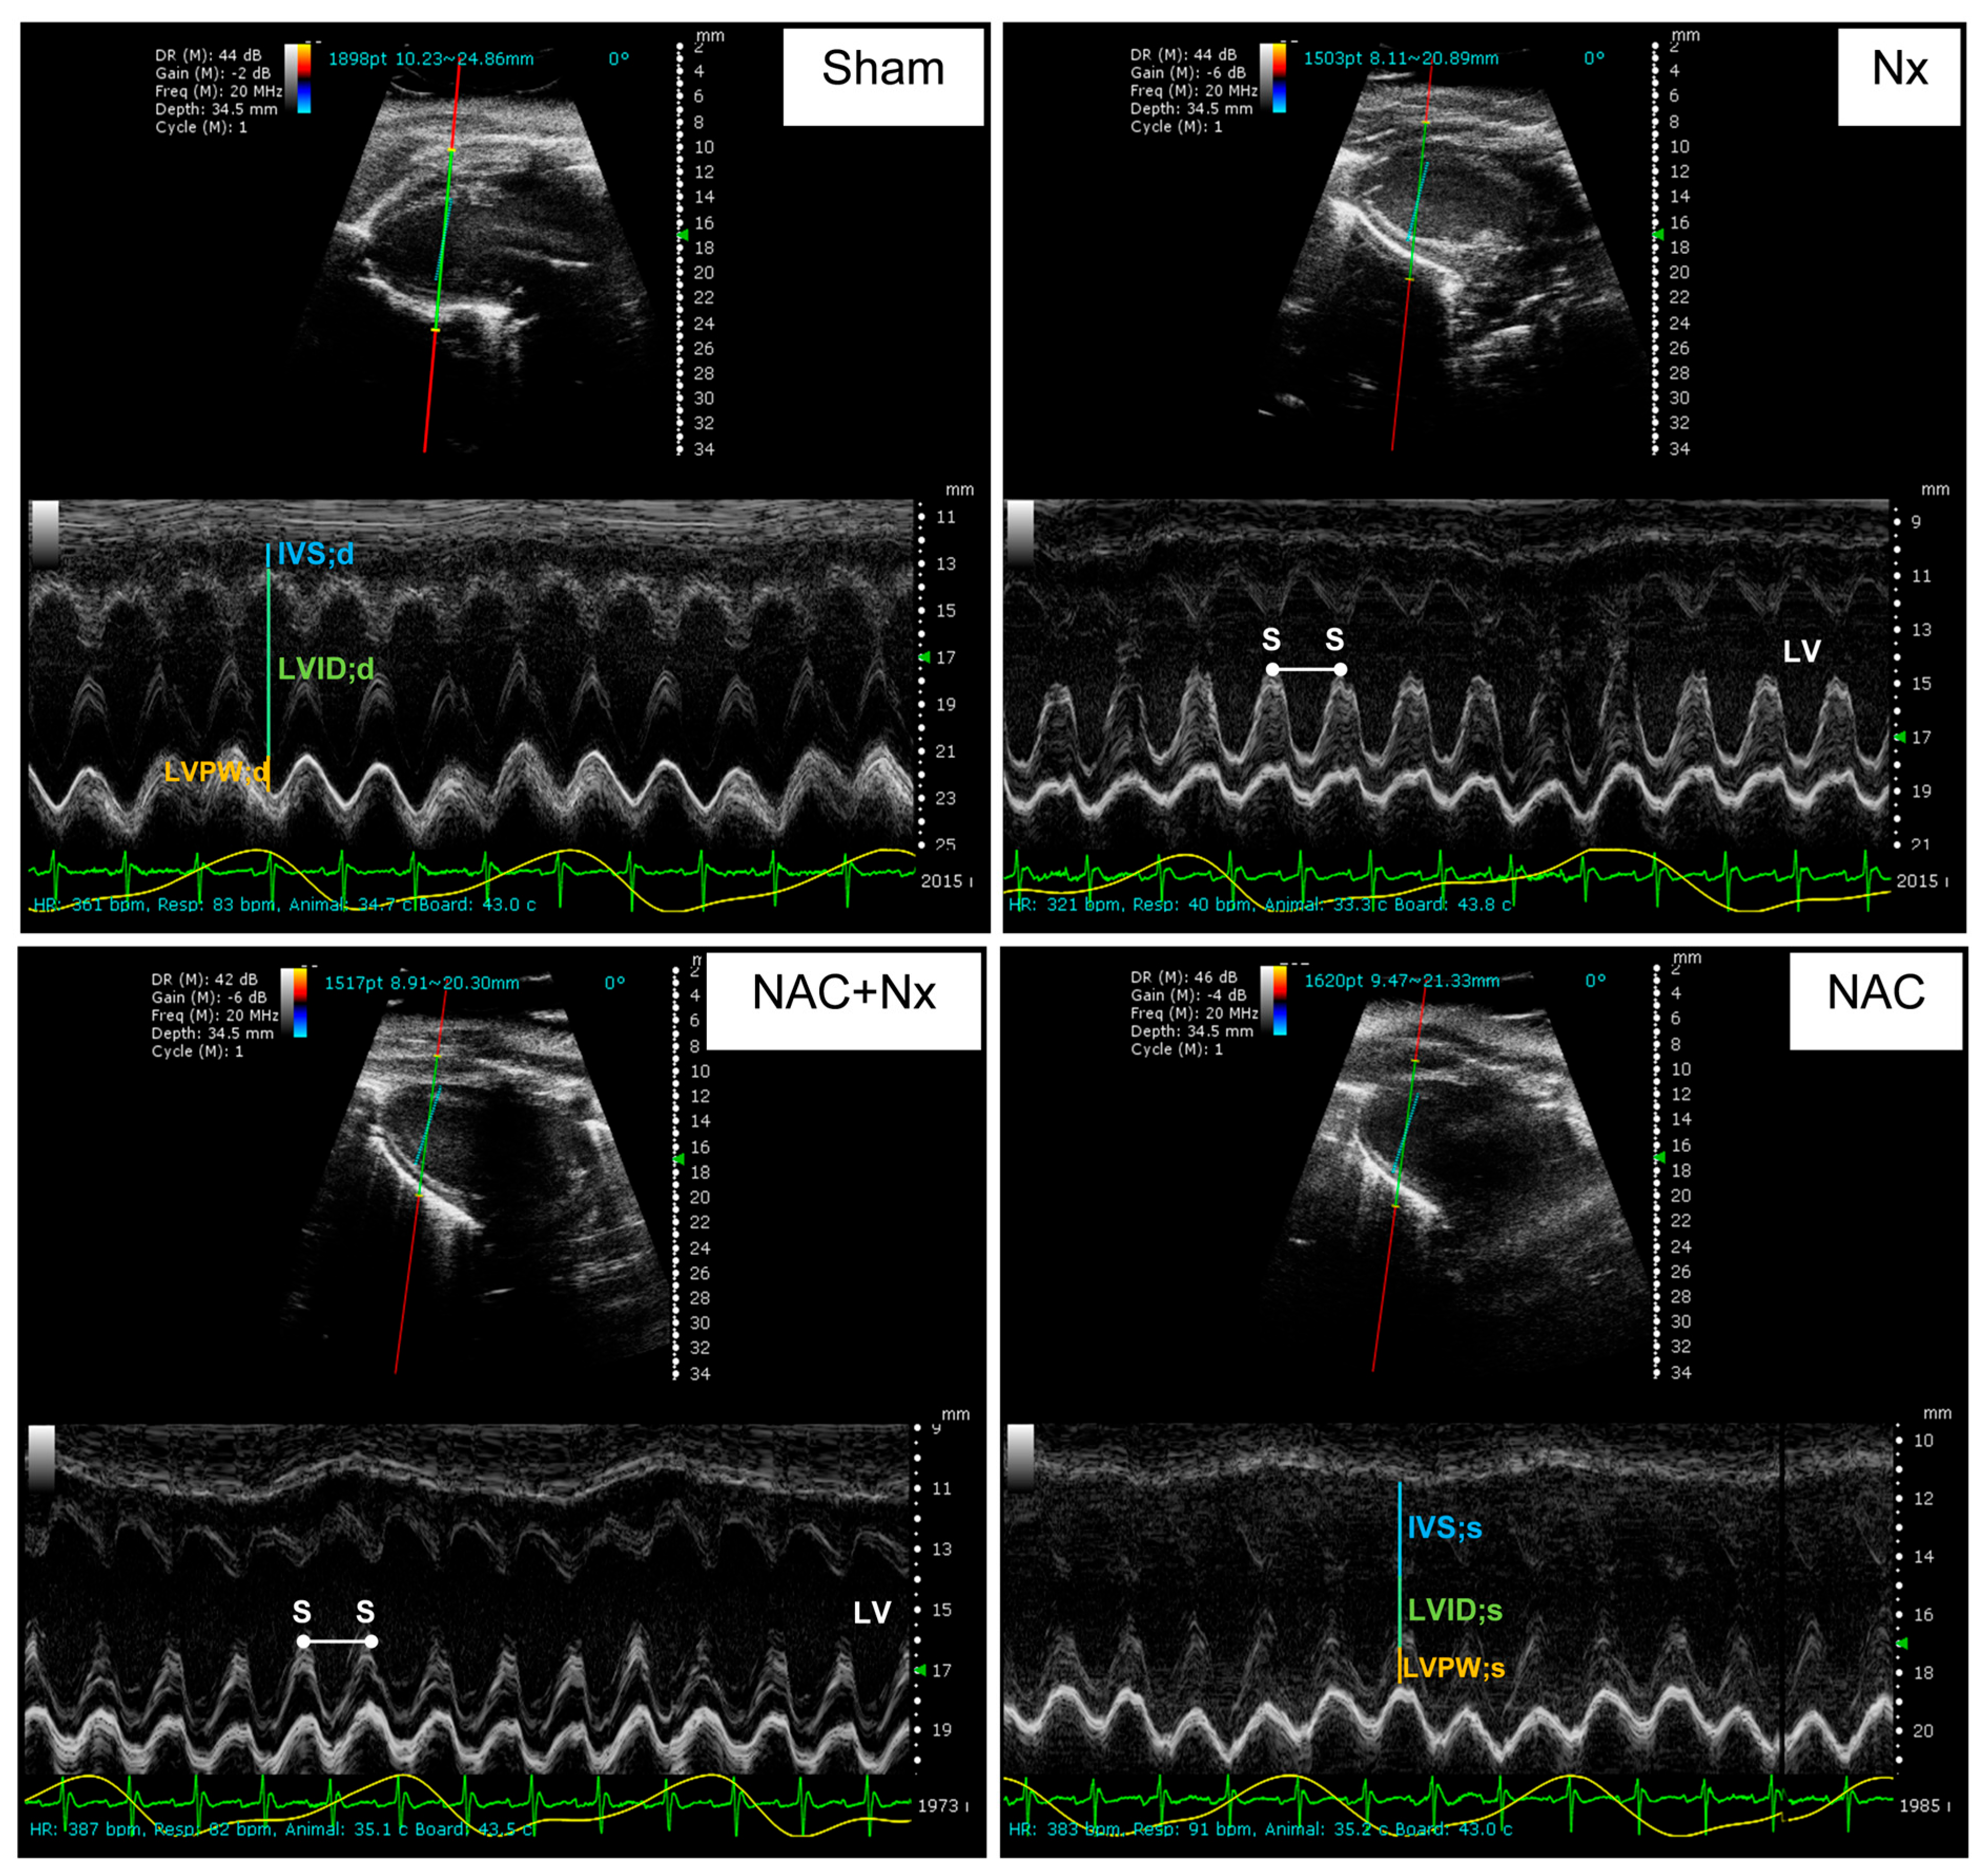

2.3. Cardio-Renal Damage Markers and Evaluation of Cardiac Function by Echocardiography

| HR (bpm) | 355.9 ± 19.3 | 365.2 ± 23.5 | 391 ± 24.6 | 365.9 ± 28.9 |

| IVS;d (mm) | 0.9 ± 0.1 | 1.1 ± 0.2 | 1.1 ± 0.3 | 1.1 ± 0.3 |

| LVID;d (mm) | 6.9 ± 0.8 | 6.7 ± 0.7 | 6 ± 0.6 | 6.8 ± 0.7 |

| LVPW;d (mm) | 1.5 ± 0.3 | 1.2 ± 0.2 | 1.3 ± 0.3 | 1.2 ± 0.1 |

| FS (%) | 57.8 ± 14.2 | 38.5 ± 7.9 * | 52 ± 9.9 *** | 52.1 ± 5.5 |

| EDV (µL) | 253.5 ± 65.9 | 236.2 ± 52.4 | 181.7 ± 39.9 | 245.6 ± 52.9 |

| ESV (µL) | 42.4 ± 37.1 | 78.2 ± 28.3 | 35.3 ± 17.5 *** | 48.3 ± 18.8 |

| EF (%) | 84.3 ± 10.1 | 66.5 ± 9.5 *,** | 80.1 ± 9.6 *** | 81.1 ± 4.6 |

| SV (µL) | 211.1 ± 42.9 | 158 ± 44.1 | 146.4 ± 36.2 * | 197.3 ± 36 |

| CO (mL/min) | 76.7 ± 17.7 | 57.2 ± 15.4 | 57.5 ± 15.1 | 72 ± 14 |